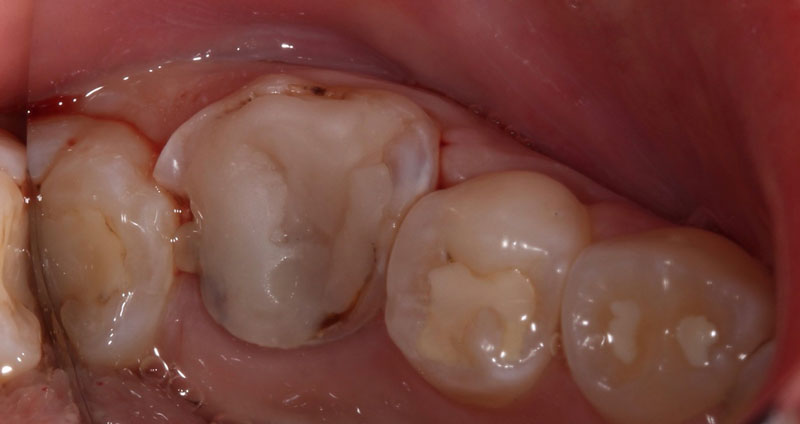

A direct pulp cap exposes a portion of the pulp tissue. This can occur due to traumatic or carious pulp exposures. In the past, when a tooth’s pulp was exposed, it almost always led to endodontic therapy. However, direct pulp capping may be feasible in specific clinical situations with modern materials that can help maintain pulp vitality, such as MTA and similar bioceramics.

Various studies have shown that direct pulp capping can be successful,2,3 and much of the research published on this topic in the endodontic community has shown that it can be a predictable procedure to maintain tooth vitality. This is even the case when a carious pulp exposure occurs in mature permanent teeth.4

Teeth with a normal pulpal response or a symptomatic reversible pulpitis response to cold stimuli have the potential to remain vital after pulp capping. However, upon cold testing, teeth that present with symptomatic irreversible pulpitis or pulpal necrosis are not candidates for pulp capping procedures. Furthermore, teeth with percussion or palpation sensitivity, or a radiolucency at the root apex, indicate the presence of apical periodontitis and are poor candidates for pulp capping.